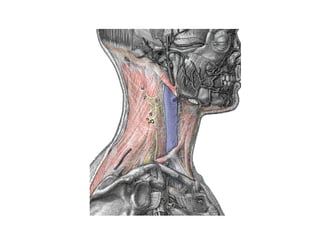

Este documento describe los principios de construcción de la arquitectura craneofacial, incluyendo el metamerismo, la simetría y la paquimería. Explica la organización peri-cavitaria del cráneo a través de columnas y vigas, y analiza las diferentes fascias profundas del cuello. También destaca la importancia de conocer la irrigación ósea con orientación quirúrgica, mencionando los principales aportes vasculares y suplementarios así como el origen, trayecto y retorno venoso de la carót